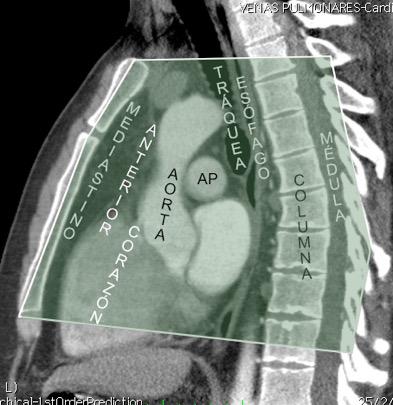

6. ÁREAS DEL MEDIASTINO EN TC